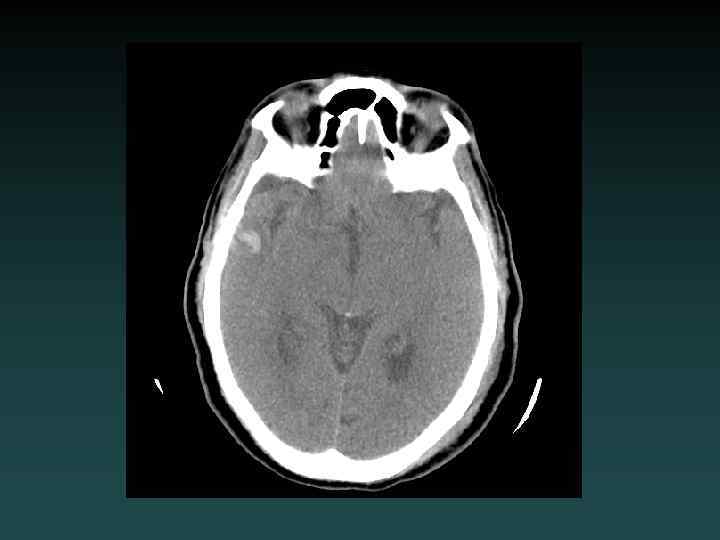

Acute Ischemia-Infarction • Subtle HYPODENSITY – Vascular distribution – Loss of grey-white margin • CT often NEGATIVE • Early CT signs – “Hyperdense MCA” – “Insular ribbon” • Role of CT: EXCLUDE BLEED • MRA or CTA useful • DSA for intervention • Early treatment may improve outcome

Watershed Infarction

Anoxic brain injury • Loss of Gray-White • Progresses with worsening edema • Pseudo. SAH • Hydrocephalus • Cisterns compressed